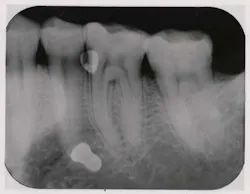

Last month we asked you to diagnose the X-ray below and send in your answers on what you think the operator may have done wrong. Today we provide you with the image’s diagnosis!Congratulations to Sarah L. Gresko, CDA, RDA, EMT-B, from Dental Studies Institute of New Jersey for correctly diagnosing last month’s image. Sarah will be awarded a $25 gift card. Great job, Sarah! Be sure to send in your diagnosis for this month’s Diagnose the X-Ray for a chance to win.

Fixer splashed on film prior to developmentX-ray answersFixer splashed on film prior to development A developed film exhibiting light blotches as shown would likely be caused from inadvertently splashing fixer on a film prior to processing, which is more likely to happen if films are manually processed. The chances of this problem occurring increase if films are removed from a packet and placed on a countertop or processor top on which fixer has not been cleaned off properly.Even if the fixer spill has dried, it can still partially or totally remove the emulsion. This may result in little or no silver left on the film to develop into an image, causing white, clear, or lighter areas on the film. To prevent this error, thoroughly clean the processor cover and countertops after processor maintenance and clean all chemical splashes up immediately. Continue reading for more tips on how to obtain high-quality images while processing manually.Tips and TricksTips for manual processorsFollow a set routineAt the beginning of each work day: